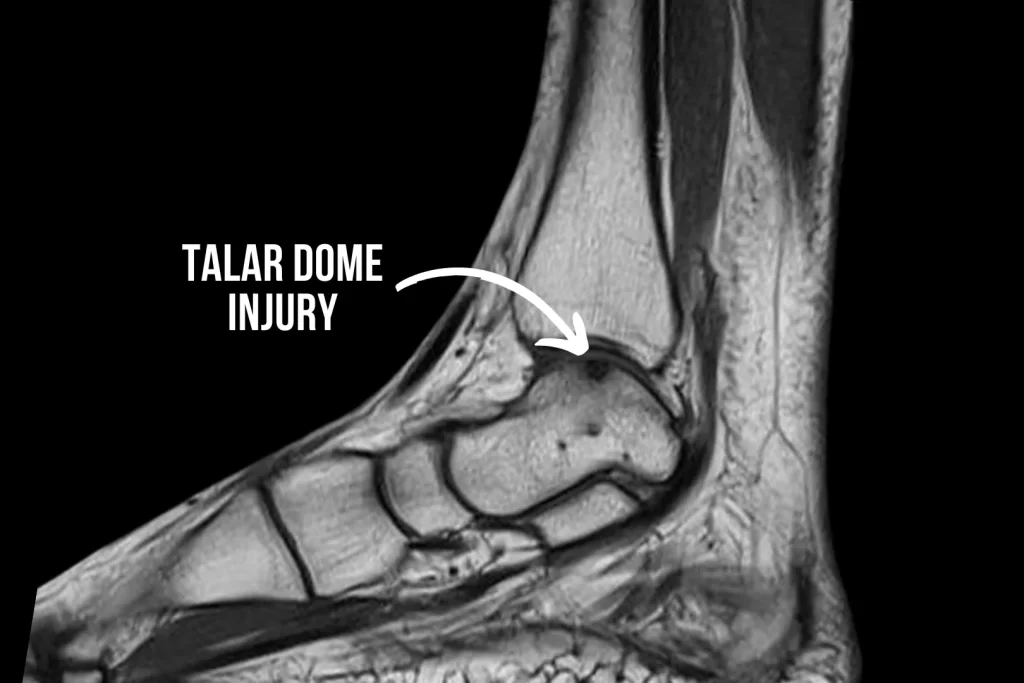

Talar dome injuries refer to a type of ankle injury that occurs when there is damage to the cartilage and bone within the ankle joint. The talus bone is located in the ankle joint and helps to support the weight of the body. When the cartilage or bone of the talus is damaged, which is often due to an impact against the shinbone, it can cause pain, swelling, and difficulty in bearing weight.

If your medical professional suspects a talar dome injury, imaging tests such as X-rays or MRI scans will be necessary. This will allow a better visualization of the ankle joint. In some cases, your surgeon may recommend an explorative arthroscopy, which is a minimally invasive procedure that involves inserting a small camera into the ankle joint to assess the extent of the damage.